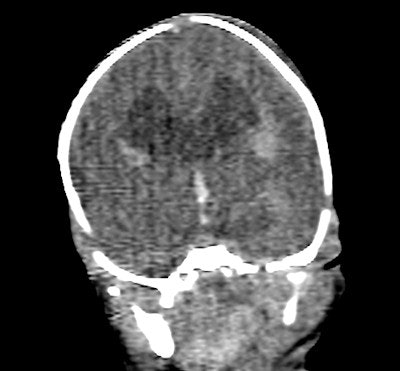

MRI is useful in the investigation of fetal abnormalities, particularly in the examination of the neural axis and soft tissues, and virtual MR autopsies are accepted by almost all parents, compared with an acceptance rate of around two-thirds for conventional autopsies, they continued. Much depends on the mother's religious background, and Muslim parents tend to be far less likely to consent to a conventional autopsy. However, the availability of MRI is limited, and a comprehensive examination with MRI is time-consuming. Because MRI signal relies upon the movement of free hydrogen atoms, signal quality is reduced in the postmortem patient due to cooling and/or refrigeration.

The dual energy image set was evaluated for the optimal image contrast and image noise. The optimal monochromatic energy level (keV) was concluded and a new image set was created for multiplanar evaluation of soft-tissue organs.

Evaluation of the heart was poor on CT, as was expected in a noncontrast postmortem study, the authors reported. The heart was correctly identified as normal in fetus 5, but much of the heart could not be commented upon, and even the great vessels were difficult to confidently identify. Significant cardiac abnormalities were identified in fetuses 2 and 3 at autopsy. The diaphragm could be seen to be intact in four of the fetuses at CT, and was intact in all fetuses at autopsy.